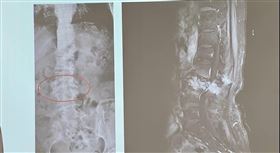

爽吃爌肉 女竟吞「整根牙籤」腸穿孔

38歲的陳小姐4月時,斷斷續續出現肚子痛的情況,直到...